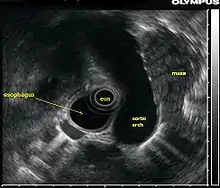

L’échographie endoscopique (EUS, acronyme de l'anglais Endoscopic ultrasound), appelée aussi ultrason endoscopique ou écho-endoscopie, est un acte médical qui emploie une source d’ultrasons au bout d’un endoscope relié à un échographe pour obtenir des images des organes internes de la poitrine et de l'abdomen. Elle peut être utilisée pour visualiser la paroi de ces organes ou pour examiner les structures adjacentes. Combiné avec l'échographie Doppler, le flux des vaisseaux sanguins avoisinants peut également être analysé.

L’échographie endoscopique s'applique le plus souvent sur le tractus digestif supérieur et sur le système respiratoire. La procédure est effectuée par les gastro-entérologues ou pneumologues qui ont eu une formation spécifique. La procédure ressemble à celle de l'endoscopie et peut être complétée par une biopsie écho-guidée.